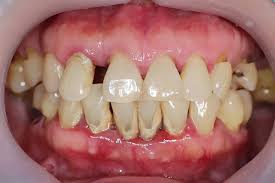

Periodontitis

results in progressive irreversible destruction of the periodontal ligament and supporting alveolar bone

JE on cementum; >4mm of pocket depth

characterization: apical migration of JE, loss of connective tissue attachment, and loss of alveolar bone

warning signs of periodontitis

accumulation of plaque biofilm and calculus

redness (erythema) and swelling (edema)

gingival bleeding

suppuration (pus)

periodontal pockets

clinical attachment loss and tooth mobility